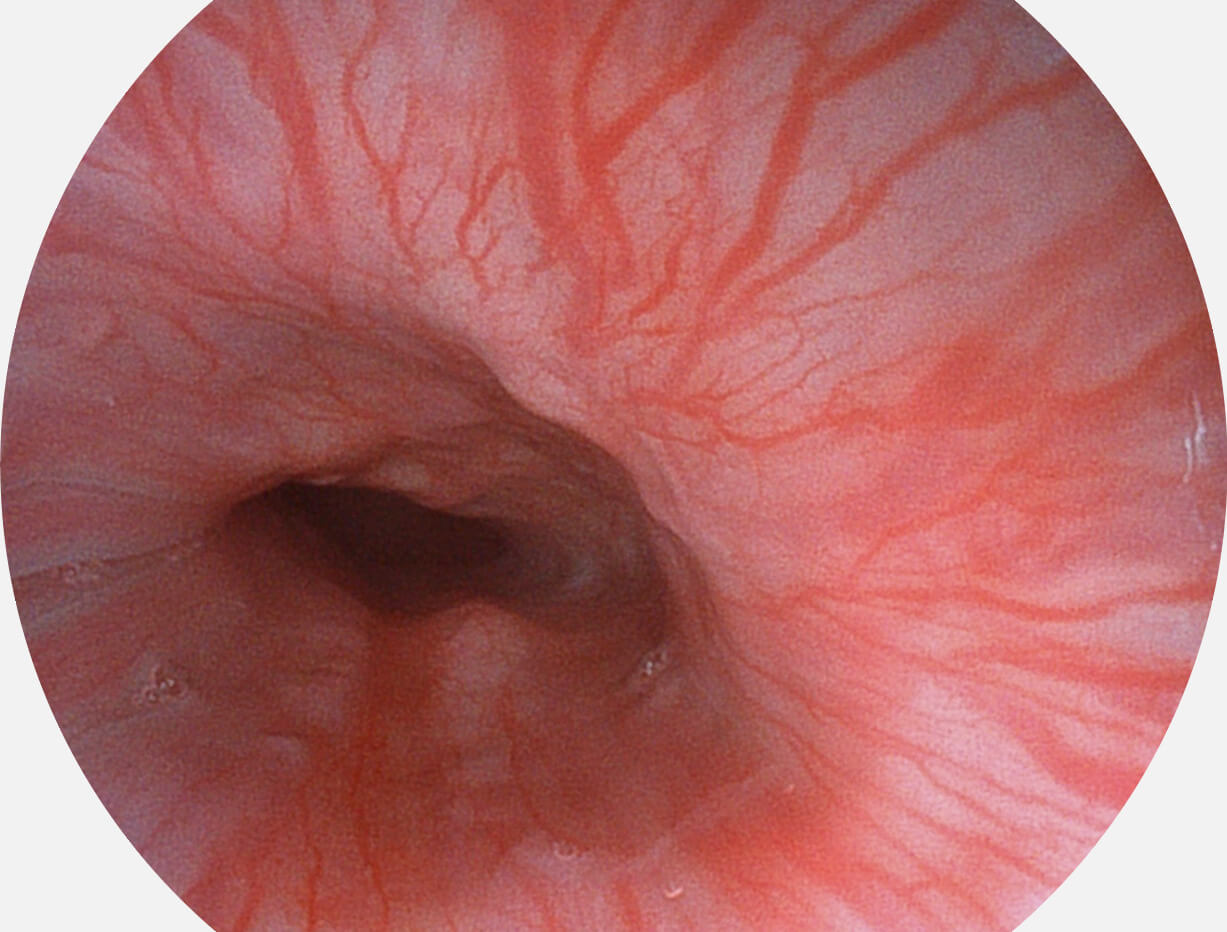

白光图像

SFI图像

图像具有高亮度、高黏膜血管颜色对比度的特点,且不改变粘液、食物残渣、粪便的基本颜色,可在中远景下进行观察,助力消化道早期疾病的诊断。